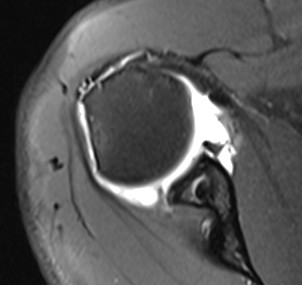

Case 1

Recurrence of instability without trauma

- anchors very high

- into glenoid face

- MRI suggests remaining inferior bankart

- no bony deficiency, no HAGL